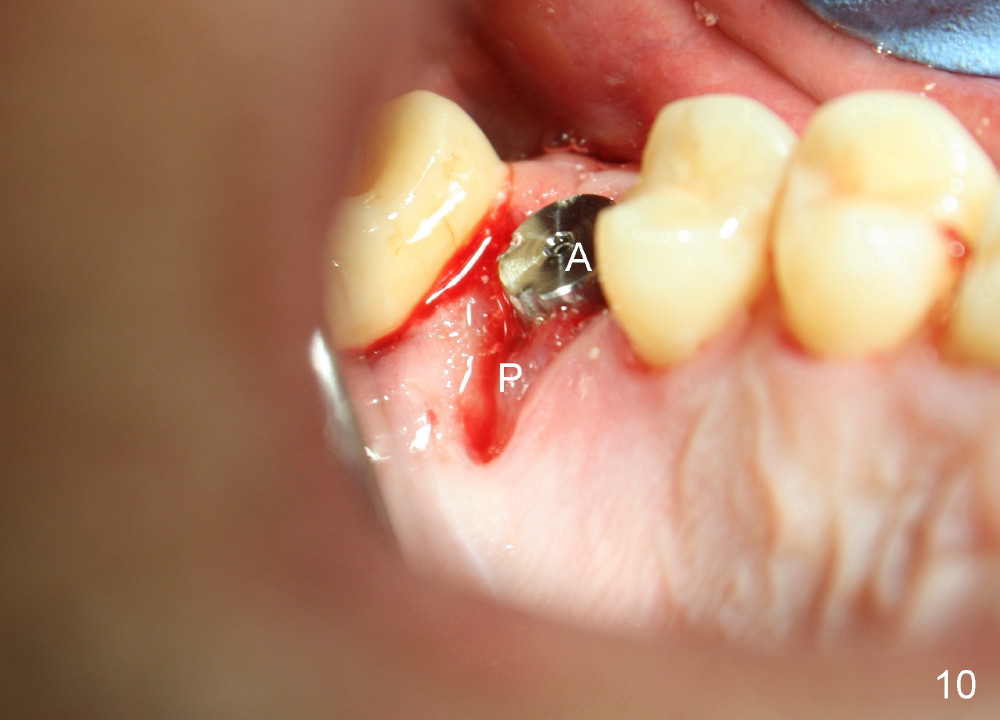

The tooth #3 has severe periodontitis with probably endodontic lesion (Fig.1,2). The patient is a 43-year-old man with apprehension of dentistry. An acute infection causes pain and tooth shift (Fig.4,5). A 7x17 mm immediate implant is planned (Fig.3). The palatal socket is shallow (Fig.6 P), corresponding to severe recessive palatal root (Fig.5 P). The osteotomy is created mainly in the buccal socket (Fig.6 B), exactly in the lingual slope of the septum. Initially osteotomes are used, followed by tap placement (Fig.7 T (4.5x20 mm at the depth of 17 mm). When the implant is placed as planned (Fig.8 I), there is more vertical contact (Fig.8 red line) than that associated with the tap (Fig.7 red line). The corresponding insertion torque is between 50 and 60 Ncm. There is only one small gap buccally, which is filled with bone graft (Fig.9 <). After the insertion of a short abutments with vertical slots (Fig.9,10 A), perio dressing is used to cover the wound. The palatal socket is expected to heal uneventfully (Fig.10 P). In fact, it does in 7 days (Fig.12 P); the bone graft in the mesiobuccal aspect is healing and stabilized (Fig.11 <). By two weeks postop, the mesiobuccal socket has healed (Fig.13 <). With removal of a diseased tooth, our body has amazing power to heal.